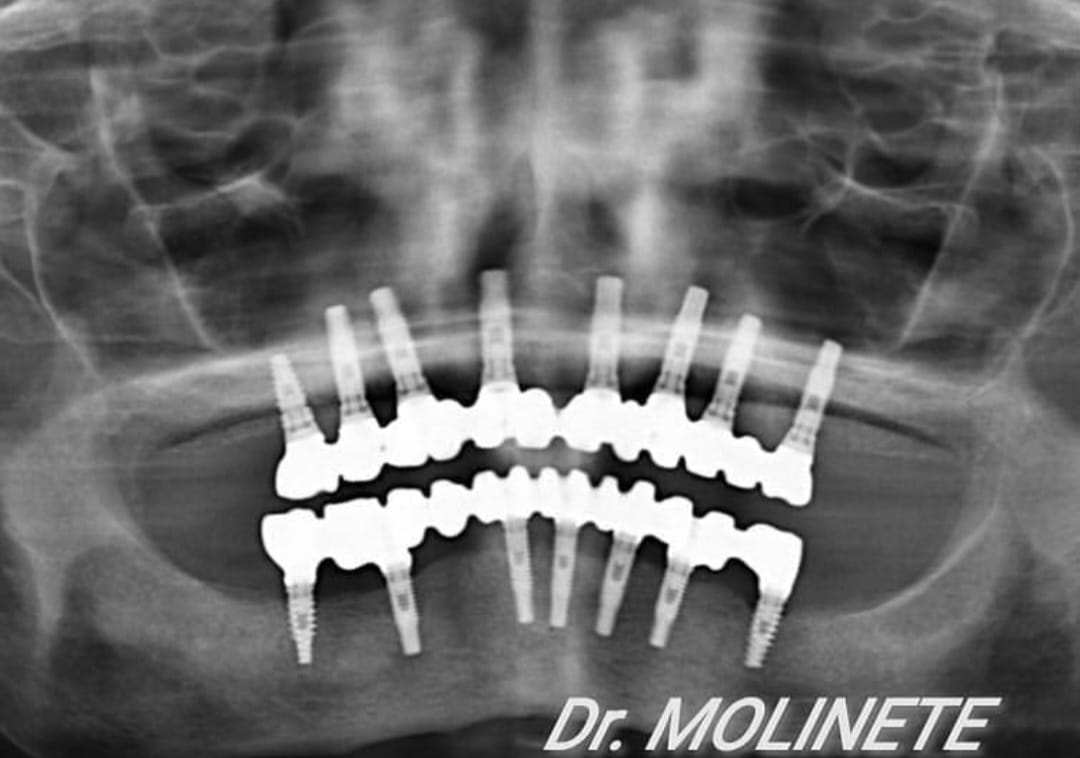

Casos de pacientes

En Clínica Dental Dr. Molinete trabajamos para que los procesos y las intervenciones sean lo más rápido y eficaz posible y con el mejor de los tratos. Tras 12 años de experiencia contamos con diferentes casos de pacientes resueltos de forma óptima.